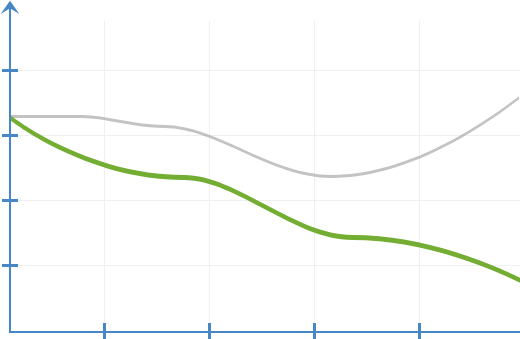

İltihabi süreçlerin

değişim dinamikleri

Prostamen kullanmadan

Prostamen kullanırken